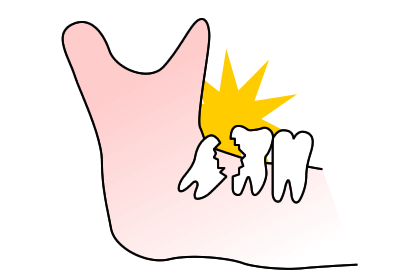

親知らずが傾斜して前の歯に引っかかっているケースは、前の歯が虫歯になりやすいので、症状が無くても早期に抜歯した方が良いことがあります。

上の写真のケースでは、親知らずが横を向いて前の歯との間に食渣が非常に挟まりやすい状態になっていました。患者さんご本人も気になっていましたが放置されていたため、左下の歯が痛くなり、来院された時には親知らずの前の歯が神経に達するほどのむし歯になっていました。

ここが虫歯になると、神経に近接しているため治療が困難になり、神経の治療を行っても予後が悪くなります。

上の写真のケースでは、むし歯が神経まで達していましたが、マイクロスコープを使用して、歯髄保存療法とダイレクトボンディングで神経を保存、歯の切削量も必要最小限で治療を行うことができました。

しかし、本来は虫歯になる前に親知らずを抜歯しておけば、このような処置は必要なかった可能性もあります。親知らずが埋伏していて気になった場合には、早めの診査・治療をお勧めします。